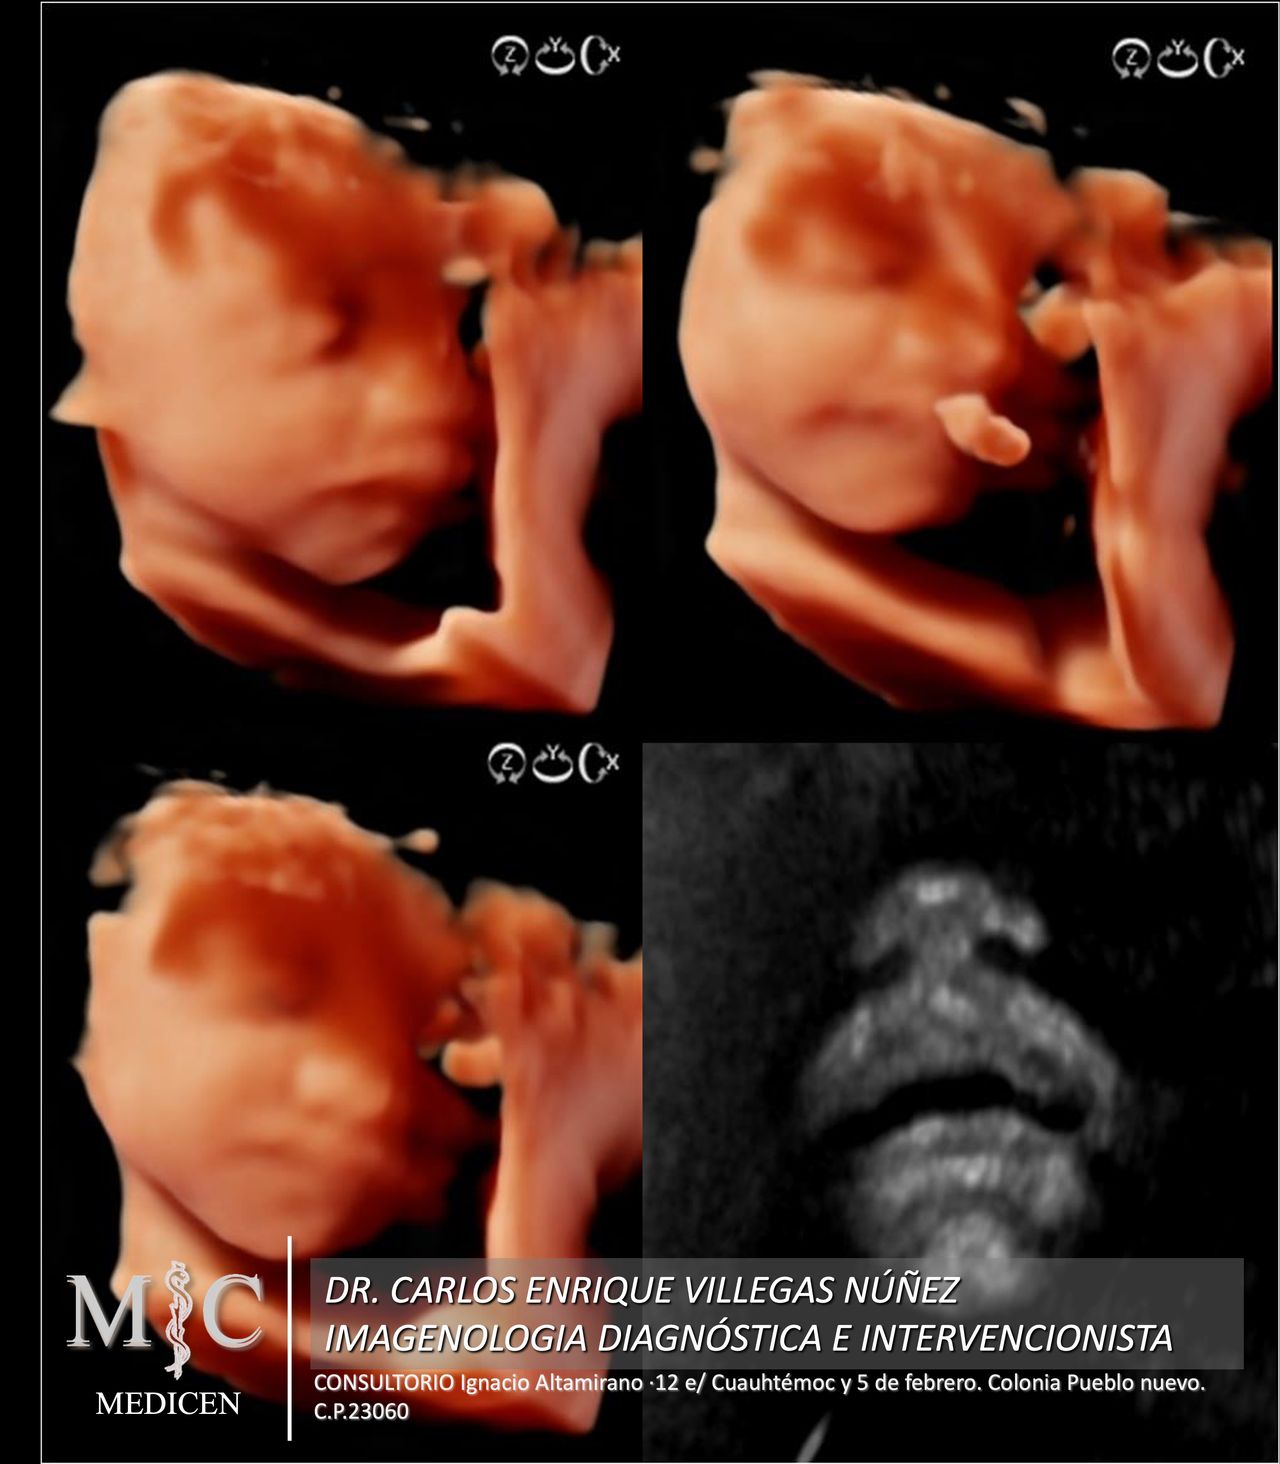

• MEDICEN Ultrasonido 3D  •

• MEDICEN Ultrasonido obstétrico  •